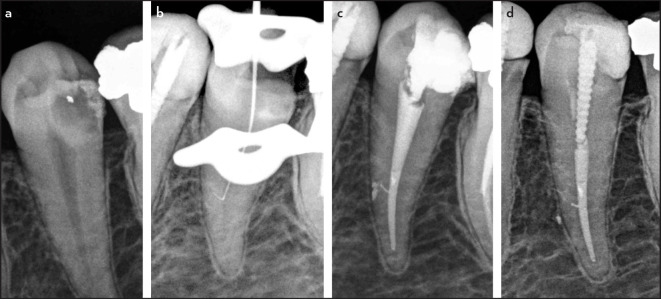

This is a series of 7 cases in which the operator penetrated lateral canals with instruments. Two teeth presented with irreversible pulpitis, 4 with necrotic pulps, and 1 with previous treatment. Except for the teeth with pulpitis, all the others were associated with apical periodontitis. The main root canal was always relatively straight, with the lateral canals at the middle third of the root. Suggestive images of lateral canal presence were seen on periapical radiographs in five cases. The clinician introduced intentionally small hand instruments in the lateral canal in 5 cases, while the penetration was fortuitous in the others. The lateral canals were obturated in all cases. Follow-up examination was possible in five cases, all of them showed evidence of successful clinical and radiographic outcomes. Introducing files into lateral canals may permit some preparation and penetration of irrigant solution, favoring disinfection and, consequently, enhancing the treatment outcome. (EEJ-2023-05-063).

Abstract Image